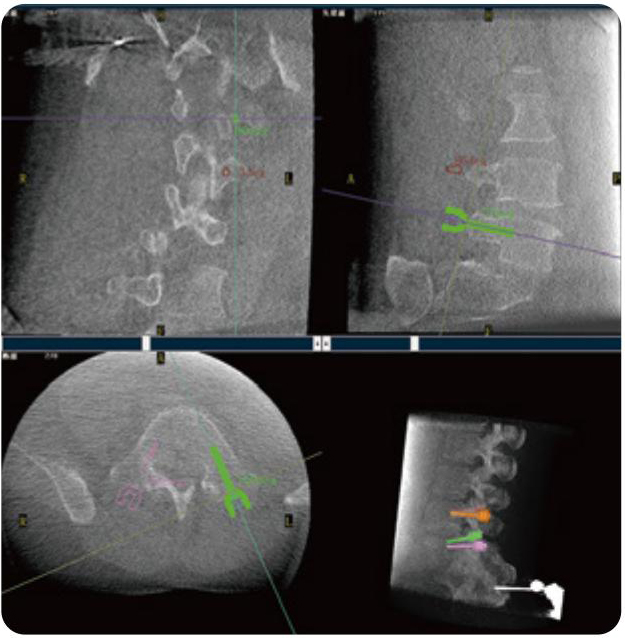

PL300B可應(yīng)用于多節(jié)段脊柱外科手術(shù),輔助醫(yī)生定位病灶部位,為脊柱外科手術(shù)(經(jīng)皮椎體成形術(shù)、椎弓根螺釘內(nèi)固定術(shù)等術(shù)式)提供術(shù)前手術(shù)流程規(guī)劃、入釘位置、角度可視化引導(dǎo),模擬仿真入釘輔助。

PL300B搭配普愛(ài)醫(yī)療自主研發(fā)生產(chǎn)的平板3D C形臂,借助一體化自適應(yīng)配準(zhǔn)( 軌跡配準(zhǔn))技術(shù),通過(guò)追蹤C(jī)形臂三維采集軌跡,自動(dòng)完成圖像坐標(biāo)建立和系統(tǒng)坐標(biāo)配準(zhǔn)。配準(zhǔn)精度更高,操作步驟少,系統(tǒng)運(yùn)作效率高。